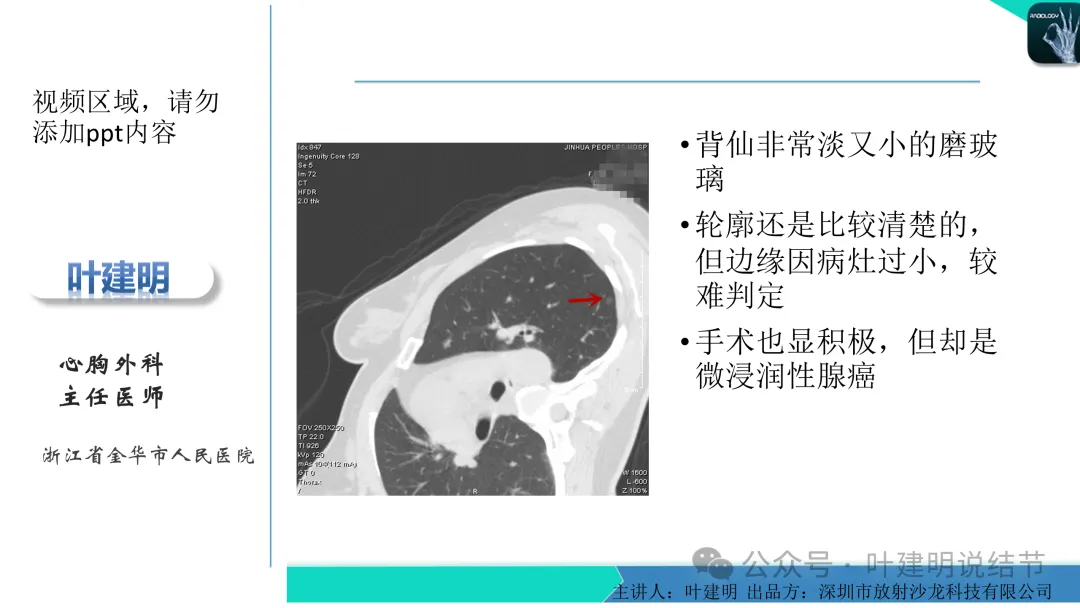

当地说考虑微浸润性腺癌的左下主病灶影像连续层面展示:

上图层面轮廓较清,但密度很淡,似见血管走行,但靠左前方的似条状磨玻璃密度与血管连着的到底是血管分支还是结节的一部分,其实并不确切。如果其实是血管分支,那病灶与它之间就不是空泡。

病灶在此层整体边缘显糊,灶内有空泡似的,瘤肺边界欠清。

边缘不平,还是灶内多发小空泡?邻近血管与之紧贴,但血管无异常走行。病灶密度很低,显糊。

中间所谓空泡更像是细支气管扩张,内壁非常光滑且圆形。

病灶边缘区淡而模糊。

某省胸科医院医生会诊后给出的意见是:左下肺后基底段(结节)达Lung-rads4B类,微浸润性腺癌可能,建议手术干预。签名的是B医生,后面给出了周一A主任肺结节门诊,周四B主任门诊。大概是团队成员,A医生是著名大咖,B医生是团队骨干成员!

这个病灶会是微浸润性腺癌吗?当然没有病理诊断,我也不能说百分之百必不会,但这样的病灶已经风险大到必得尽快手术切除干预了吗?显然还早着呢:1、影像不是典型的结节状;2、边缘与轮廓模糊不清;3、灶内似有细支气管扩张(更容易是细支气管扩张伴少许周围炎或肺泡上皮增生);4、血管邻近走但无牵拉影响;5、没有实性成分,没有锐利毛刺,没有胸膜牵拉,没有血管进入,没有任何倾向风险性高的影像特点。我一直强调:肺结节是否要干预处理,不要纠结于最后病理是什么,而要看风险高低;而风险高低的最重要术前判断依据一是随访有无进展,二是有没有实性成分。只要没有肉眼可见的影像上的实性成分,风险就是低的!何况病理也是人看的,原位还是微浸润,不典型增生还是原位有时也在一念之间。

早在2020年时,我受邀在《放射沙龙》做过一个系列的精品课,当时专门总结分析过各类良恶性肺结节与肿块的影像特征,这是当时关于微浸润性腺癌影像特征的分析,今天看来仍基本不太需要改变,大家有兴趣的可以参考: